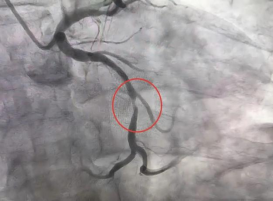

王女士,因“反复心累、胸闷5+年,再发伴头晕2小时”入院,入院后行冠状动脉造影检查,冠状动脉造影显示:LAD(前降支)中段弥漫性狭窄,最重处狭窄约90%,确诊为冠心病。随后,内科一病区医生团队为患者实施了冠状动脉支架植入术,术后,王女士的心累、胸闷症状明显缓解,困扰她的头晕也消失了。

(术前) (术后)